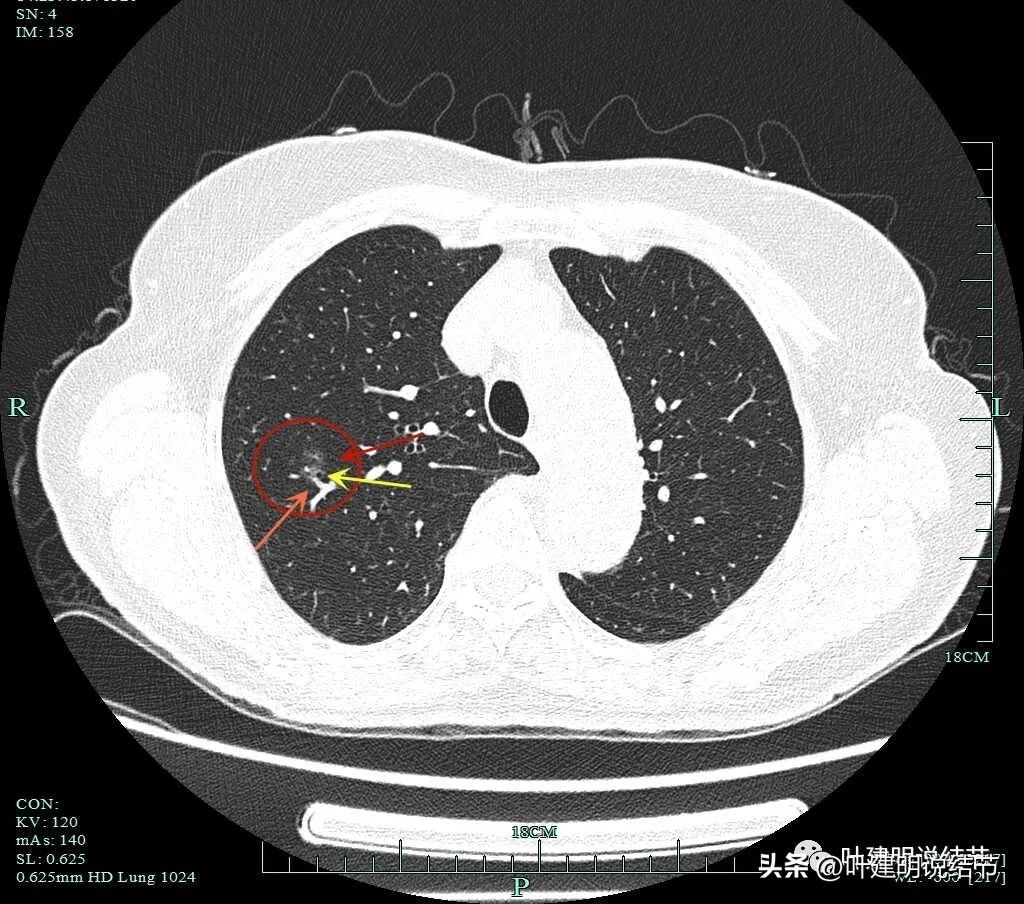

病灶分叶、细支气管扩张,微小血管进入;整体轮廓较清。

上图这个视角清楚显示灶内的空泡征是扩张的细支气管。而且灶外细些,灶内更远离肺门,反而扩张,说明病灶有牵拉力呀!

边缘有毛刺征,灶内密度欠均。